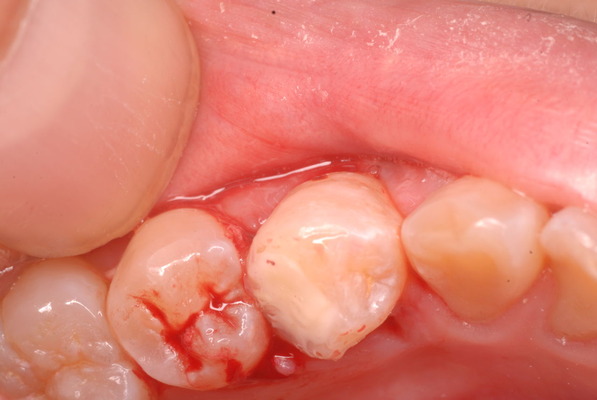

まだ虫歯は残っていますが危険なので除去せずにそのまま消毒して鎮静セメントを挿入しました。

隣の歯との間をプラスチックで閉鎖し、唾液の侵入を防ぎました。でもまだ虫歯は残っています。

鎮静セメントを詰めて終了しました。後は神経の傷が治癒するのを待ちます。半年以上はかかります。